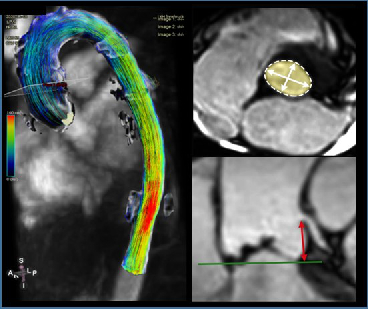

Cardiovascular MR Imaging

Agnes Mayr, Christian Kremser, in cooperation with the Department of Cardiology

c) 4D Phase Contrast Flow Measurements

- Patients with different grades of aortic valve stenosis: comparison of 4D flow-assessed stenosis severity with 3D echocardiography and invasive measurements.

- Patients with cryptogenic stroke: recording turbulent kinetic energy, changes in flow patterns and regional wall stresses as well as occurrence of a vortex-shaped flow along the thoracic aortic wall, in order to optimise the elucidation of potential cardioembolic sources.